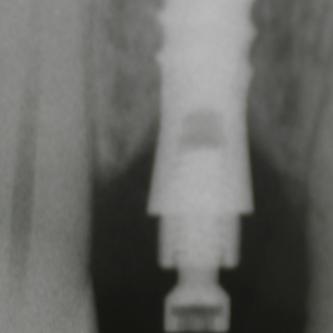

Exemple 7: Un implant au niveau de la deuxième prémolaire inférieure gauche.

Exemple 7: Le moignon vissé sur l'implant.

Exemple 7: La couronne en place

Exemple 7: vue depuis dessus